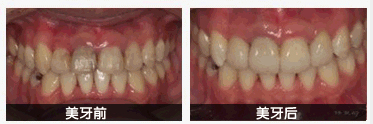

中韩·唯美口腔牙齿修复案例

选择好的烤瓷牙固然是很好的,适合自己的才是更好的。中韩·唯美口腔医院团队对治疗都积累丰富的临床经验,借康复患者之间的口碑相传,声名远播,全国患者纷纷前来就诊。您的更佳选择。更多牙齿健康相关知识,您可以咨询在线医生。